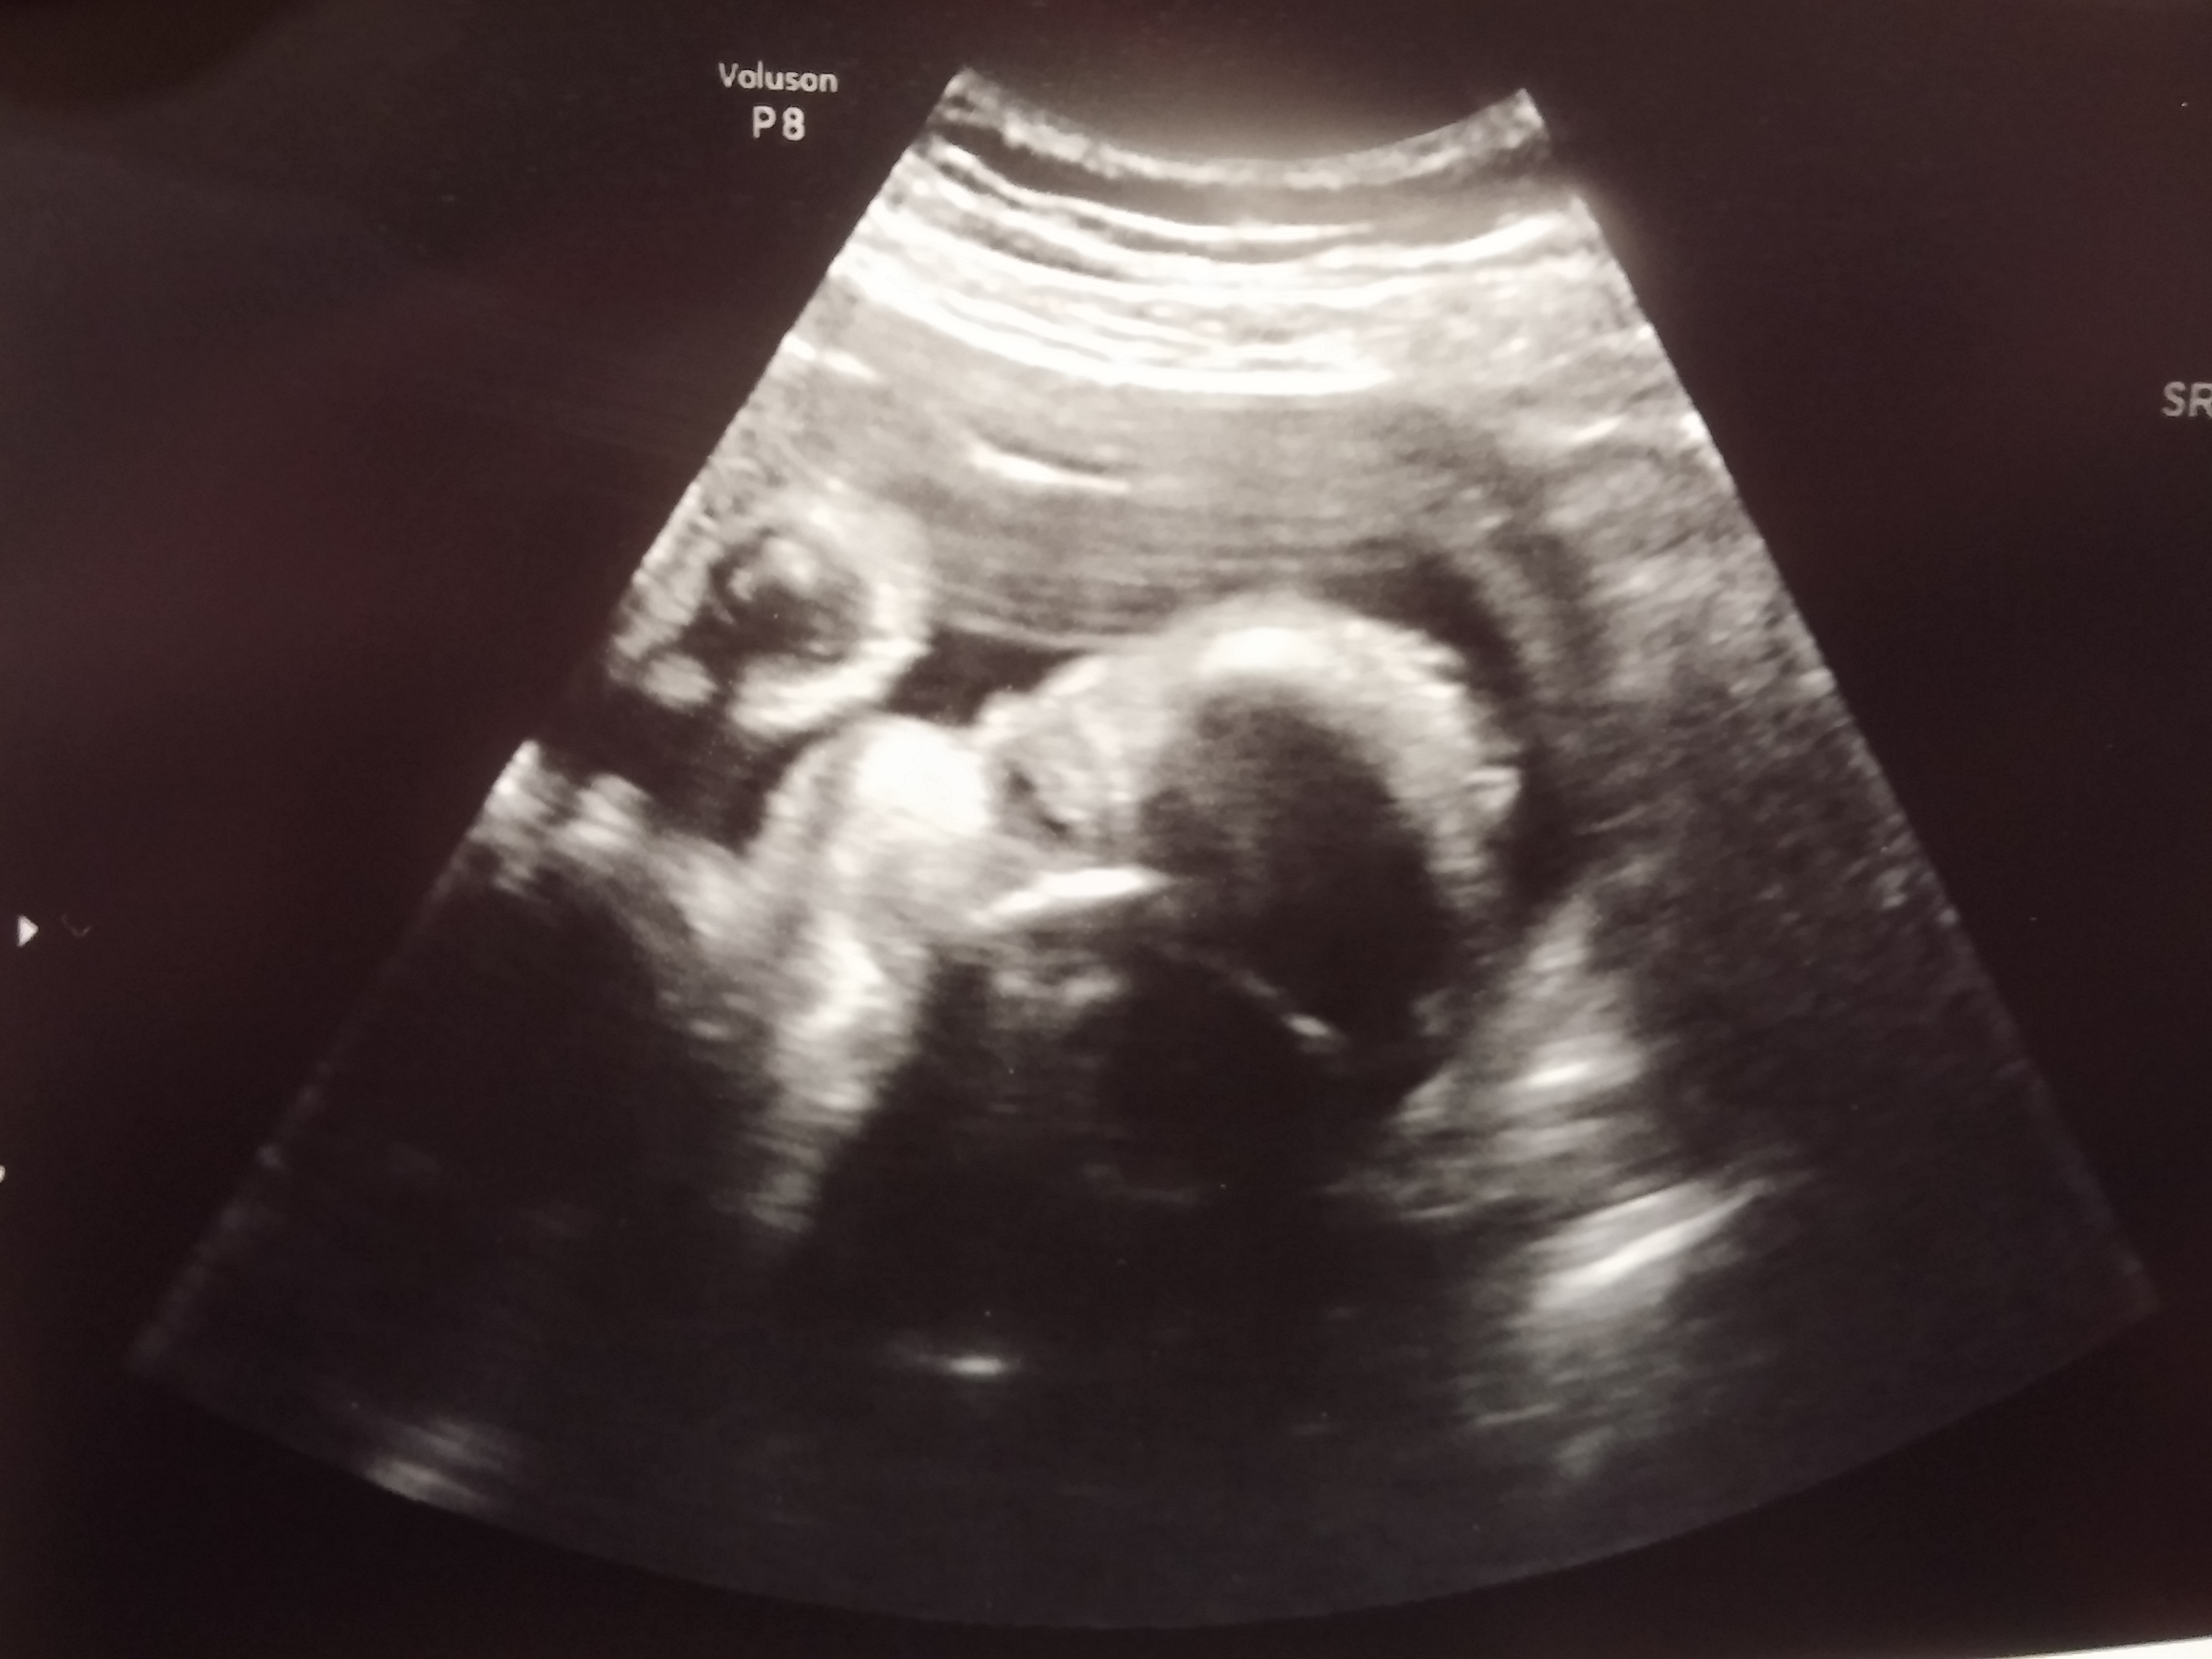

I have to AW a little though. We had our 32 week check up yesterday and follow up u/s and I got some cute pics of little man. His CP cysts are completely gone and he's measuring right on track. He's head down too which is why I'm feeling him kicking me in the ribs. He weighs about 4 lbs. We could see him opening and closing his little mouth too, which was the cutest thing ever. I can't believe how much I love him already!